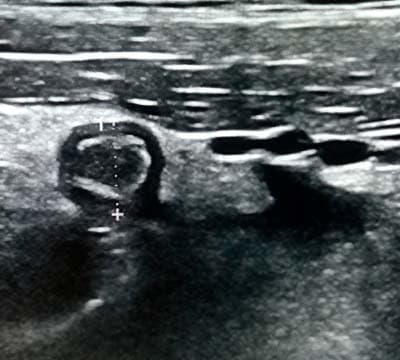

При поперечном сканировании напоминает «мишень»: внутреннее гиперэхогенное кольцо отображает воспаленный и отечный подслизистый слой; наружное гипоэхогенное (или анэхогенное) кольцо отображает воспаленный и отечный мышечный слой (см. рис. 2, 2а).

Рисунки 2, 2а. При поперечном сканировании аппендикс имеет вид «мишени».